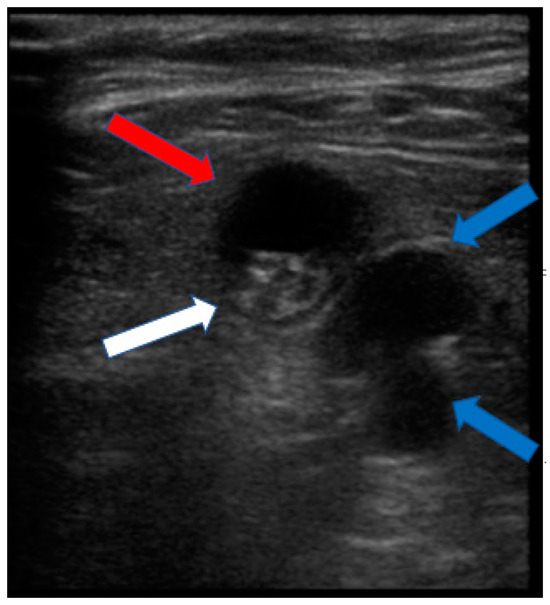

2.1. Preoperative Evaluation